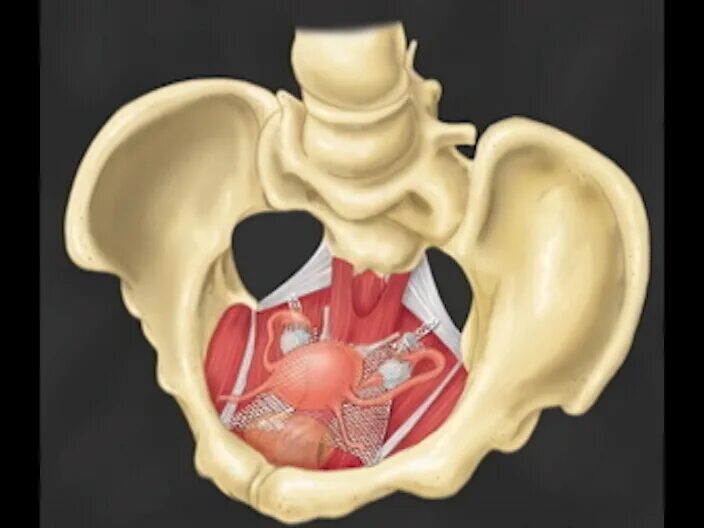

Опущение органов малого таза у женщин операция